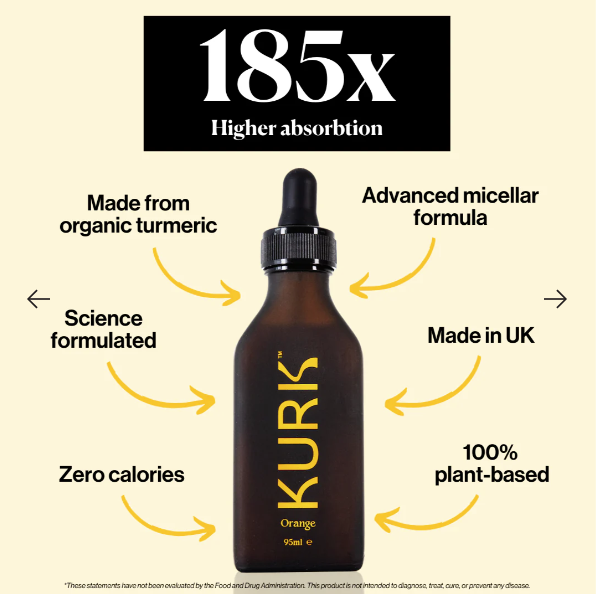

The challenge with curcumin has always been bioavailability — it’s poorly absorbed on its own. Kurk’s Curcumin addresses this through formulation strategies designed to improve absorption and utilisation.

Absorption & Bioavailability (Why This Matters)

Not all curcumin products are equal. Poor absorption means poor results.

Kurk’s Curcumin is formulated to:

This is the difference between “taking turmeric” and actually experiencing benefits.